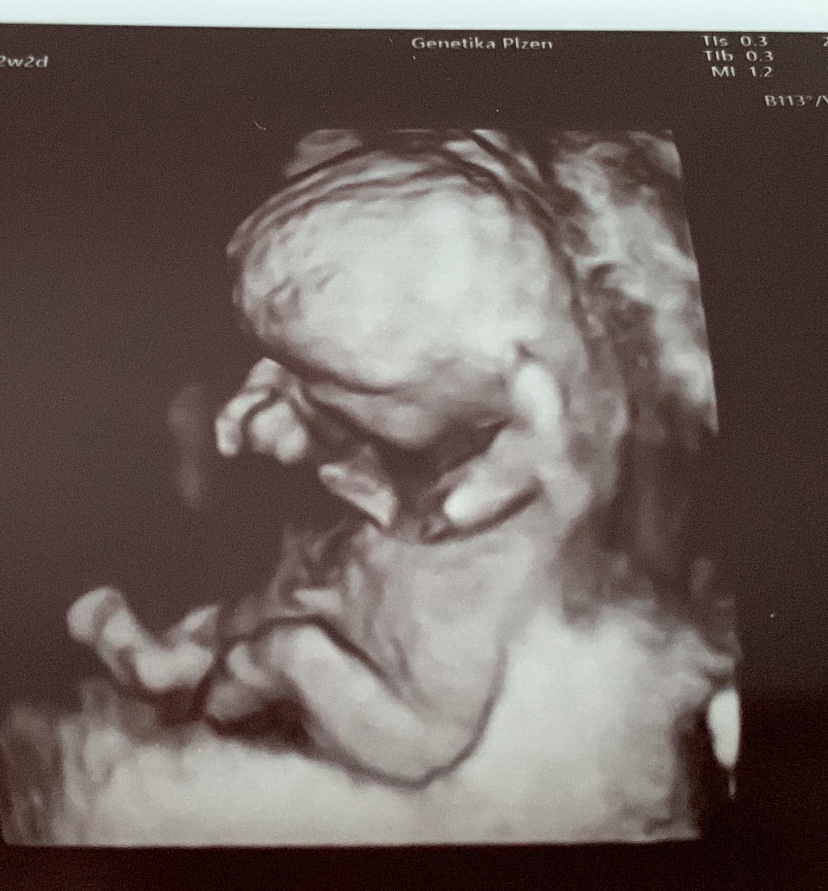

@reeeza tak náš malý měl šíjové projasnění 5,4 a limit je 2,5. Doktor se se mnou bavil v podstatě tak, že je to škoda, protože plod jinak vypadá dobře, ale hned se mnou probíral možnosti případného potratu. Na výsledky jsme čekali 3 týdny, spousta stresu a pláče a je to spokojené, usměvavé miminko. Takže i kdyby tam mělo miminko více tekutiny, nemusí to vůbec nic znamenat. 🙂 Testy jsem si platila neinvazivní a dělali to v Plzni. Tam je na to specializované pracoviště.

@reeeza jinak nase fotky z prvotrim screeningu vypadaly takto..